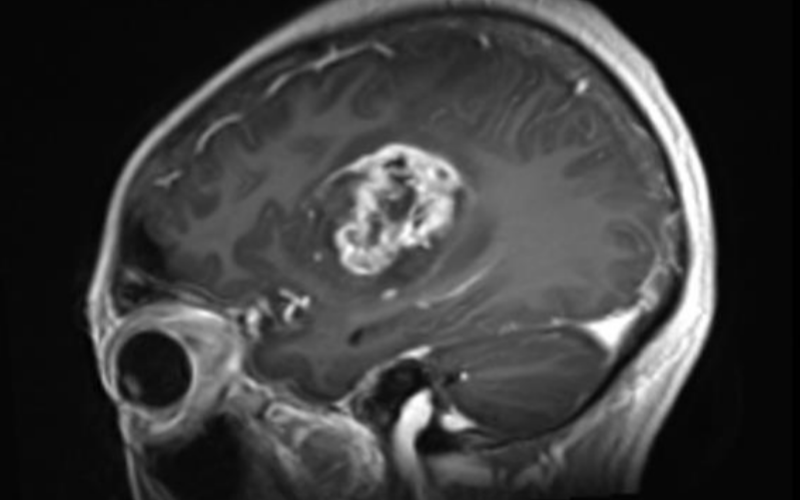

重慶大學附屬腫瘤醫(yī)院神經(jīng)外科手術(shù)集錦:Endoport下腦室巨大占位性病變切除術(shù)

發(fā)布日期:2025/7/21

病例分享:重慶大學附屬腫瘤醫(yī)院神經(jīng)外科Endoport下切除左額深部基底節(jié)區(qū)膠質(zhì)瘤

發(fā)布日期:2025/7/4

隨著各種新技術(shù)、新器械的日益發(fā)展,神經(jīng)外科手術(shù)的微創(chuàng)理念逐步得到實現(xiàn)。當代神經(jīng)外科學,在微創(chuàng)理念的引導下已發(fā)展為微創(chuàng)神經(jīng)外科。微創(chuàng)神經(jīng)外科要求術(shù)者在手術(shù)中,盡量減少對患者腦組織的醫(yī)源性干擾和損傷。。。